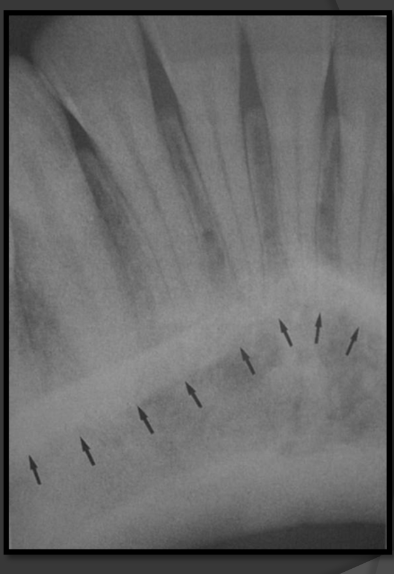

How does the external oblique ridge present in a radiograph?

Always the highest opaque line of the mandible that follows the contour of the jaw.

How does the internal oblique ridge present in a radiograph?

The second highest opaque line on the mandible that follows the contour of the jaw. Will always be below the external oblique ridge

How does the mandibular canal present in a radiograph?

It is a radiolucencent band that follows the contour of the mandible that runs under the teeth.